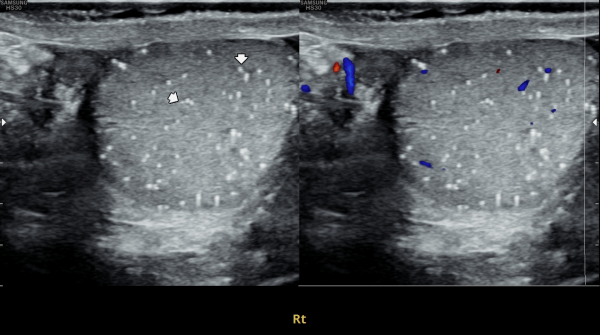

전립선의 경직장 전립선 초음파상 우측 전립선의 순환장애로 전립선의 이행구역내 탈락된 상피세포들이 쌓여 결절을 형성하고 전립선액 즉 구연산과 섬유소용해소 그리고 산성포스파타제등의 순환 장애로 전립선의 낭종이

관찰되는 사진입니다.

This transrectal prostate ultrasound image shows that, due to impaired circulation on the right side of the prostate, exfoliated epithelial cells have accumulated in the transition zone, forming a nodule. As a result of poor circulation of prostatic fluid—such as citrate, fibrinolysin, and acid phosphatase—prostatic cysts are also observed.

첫 내원 당일 검사한 고환의 초음파 사진상 앉아서 생활하는 직업상 고환 동맥의 순환 장애로 죽상동맥경화증의 소견을 보여 식이요법과 운동요법을 말씀드리고 정관의 표적 치료를 시작한 사진입니다.

On the day of your first visit, the testicular ultrasound showed signs of reduced blood flow in the testicular artery, likely from long hours of sitting. This may have caused early signs of atherosclerosis. We discussed healthy lifestyle changes, including diet and exercise, and started targeted treatment for the vas deferens.